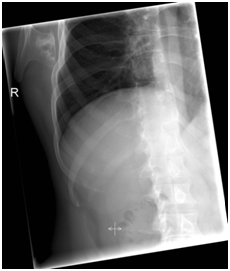

In our outpatient department a 33-year-old male presented with complaints of continuous pain around his right shoulder and scapula. The pain developed gradually over the last 2 years, making it impossible to sleep on his right shoulder and he had complaints of pain during daily labour. When moving his right shoulder, crepitation was noted by the patient around the right scapula. Family history was not contributory and there was no history of trauma. A clinical examination showed an asymmetry of his scapulae with a wing-like prominence of his right scapula (Figure 1). Scapulothoracic crepitus was noted when abducting his right shoulder. A full range of motion was found in both shoulders. Radiographic evaluation showed an irregular bony structure extruding from the scapula (Figure 2). Computed tomography (CT) revealed an osteochondroma along the medial border on the ventral surface of the right scapula (Figure 3). In addition a magnetic resonance imaging (MRI) was performed, showing a bone lesion originating from the anterior side of the scapula with slight bursa formation, most likely to be an osteochondroma (Figure 4). There were no signs of malignant transformation. Since the lesion prevented the patient from performing his job and the complaints of his shoulder worsened over time, surgical resection was proposed.

Figure 2 Pre-operative radiograph of the right shoulder, showing bony mass arising from the infro medial region of the scapula.